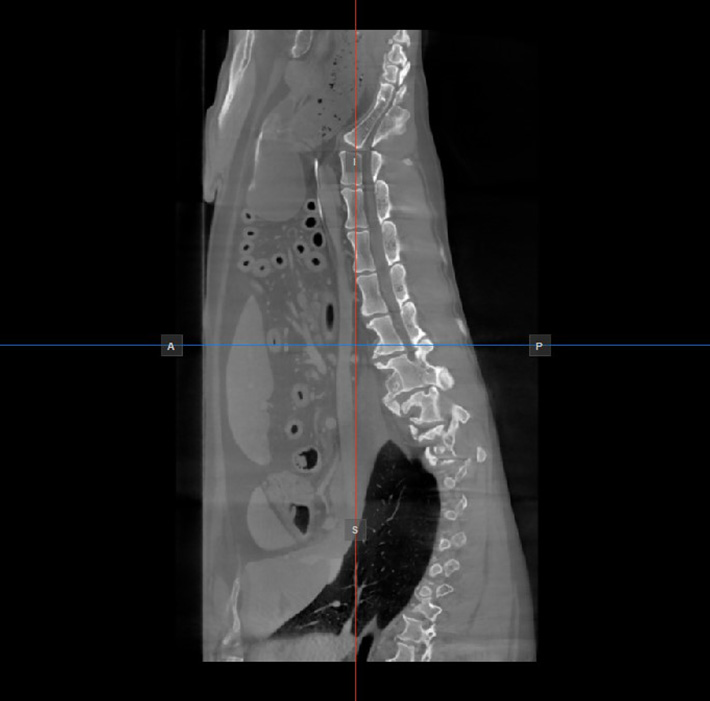

Image Orientation and Image Planes

The position and intersection of the other two image planes not represented in the active viewport is indicated by two vertical and horizontal lines called slicers. The endpoints of each slicer are labeled with a letter that corresponds to the appropriate direction/side of the 3D volume, based on the RAS coordinate system.

Only four sides of the available six are indicated on each 2D viewport. The labels and the corresponding side are the following:

• Patient Right (R), indicating the right side of the body

• Patient Left (L), indicating the left side of the body

• Anterior (A), indicating the front side of the body

• Posterior (P), indicating the back side of the body

• Superior (S), indicating the top side of the body

• Inferior (I), indicating the bottom side of the body

../../_images/image139.jpg